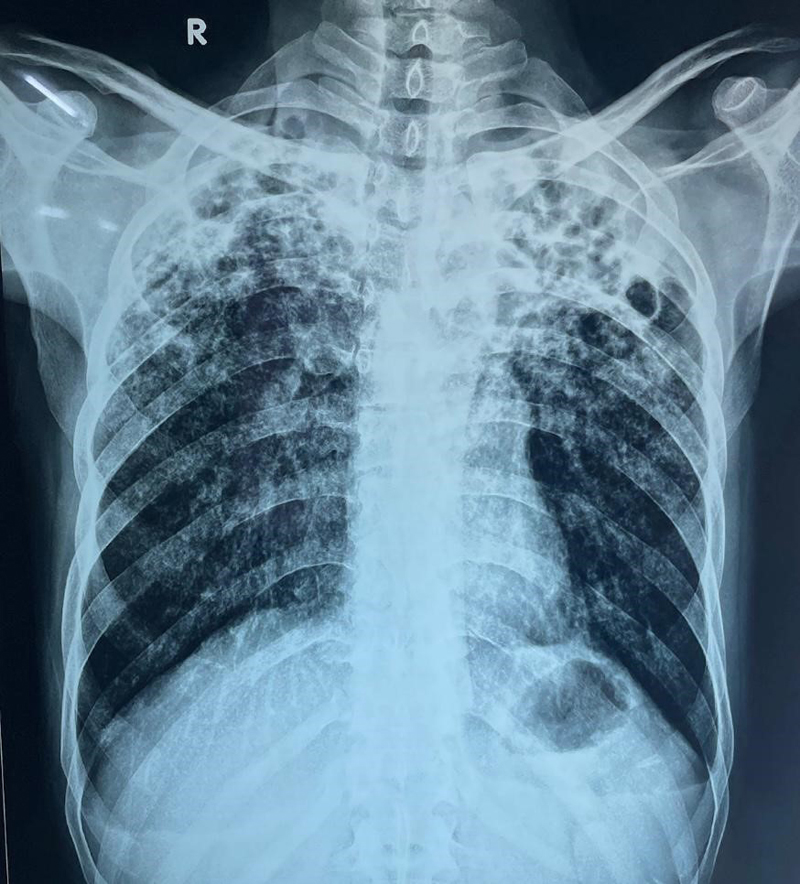

This patient came to the Respiratory Medicine outpatient department with complaints of cough with expectoration and throat pain over 15 days, a change in voice (hoarseness) with difficulty in swallowing (solids > liquids) for 1 month, weight loss of 9 kgs in 2 months, regurgitation (liquids > solids) for 15 days. A chest X-ray revealed bilateral heterogenous opacities (Figure 1) and sputum was sent for routine investigations. Sputum CBNAAT report detected M. tuberculosis without RiF resistance. Computed tomography of the neck revealed asymmetric heterogeneously thickening, involving both lateral glosso-epiglottic folds, the epiglottis, aryeepiglottic folds (R > L) with obliteration of pyriform fossa. Cervical nodes were mildly enlarged, which suggested a possible neoplasm. The patient underwent endoscopy that revealed ulceroproliferative growth on bilateral aryepiglottic folds, arytenoids, pyriform fossa, and vocal cords (Figure 2).

Figure 2

Figure 2. Bronchoscopic image reveals inflammatory nodules on the aryepiglottic folds, arytenoids, pyriform fossa, and vocal cords.